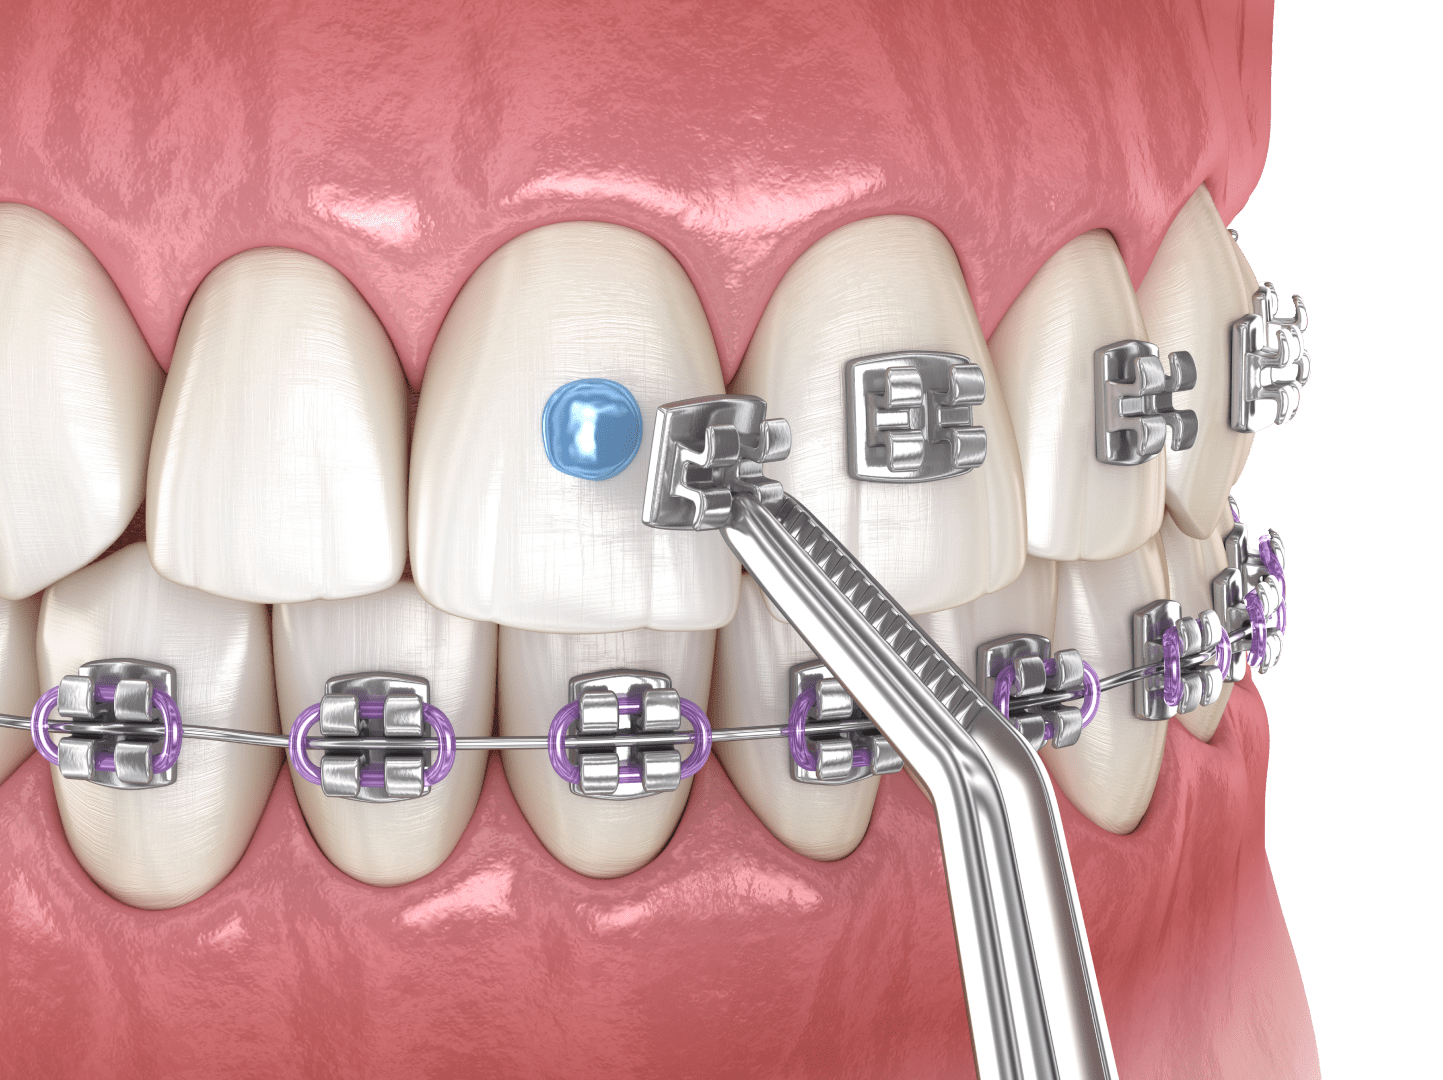

Брекети

Брекет-система — це найефективніший метод вирівнювання зубів різної складності. Класичний апарат (самолігуючі брекети) складається з маленьких замочків, які кріпляться на кожен зуб і фіксують у пазах металеву дугу. Лігатурна конструкція включає також еластичні резинки або кільця з дроту.

Вирівнювання зубного ряду відбувається за рахунок натягнутої, як пружина, дуги, яка, прагнучи повернутися в початкове положення, чинить тиск на зуби та зміщує їх за собою.

Переваги:

- висока ефективність, зокрема в складних клінічних випадках;

- застосовується і для дітей, і для дорослих;

- широкий вибір конструкцій, завдяки чому кожен пацієнт може підібрати для себе оптимальний варіант за ціною та зовнішнім виглядом;

- швидка адаптація після встановлення.

Недоліки:

- металеві брекети помітні в ротовій порожнині, але досягти естетичного вигляду можна за допомогою сапфірових чи керамічних систем;

- конструкція для вирівнювання зубів вимагає певного догляду та обмежень у продуктах харчування;

- при недостатній гігієні ротової порожнини можливий розвиток карієсу або запалення ясен.